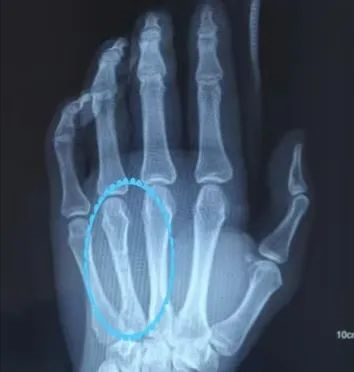

这名年轻男性患者因“左侧第四掌骨骨折”寻医问诊,因顾虑二次手术取出固定钢板还要再痛一次,就到处询问偏方,毕竟痛的事情一次就够了,不要再来一次。可是哪里不受皮肉之痛呢?还是咬牙坚持吧!

术前 术后